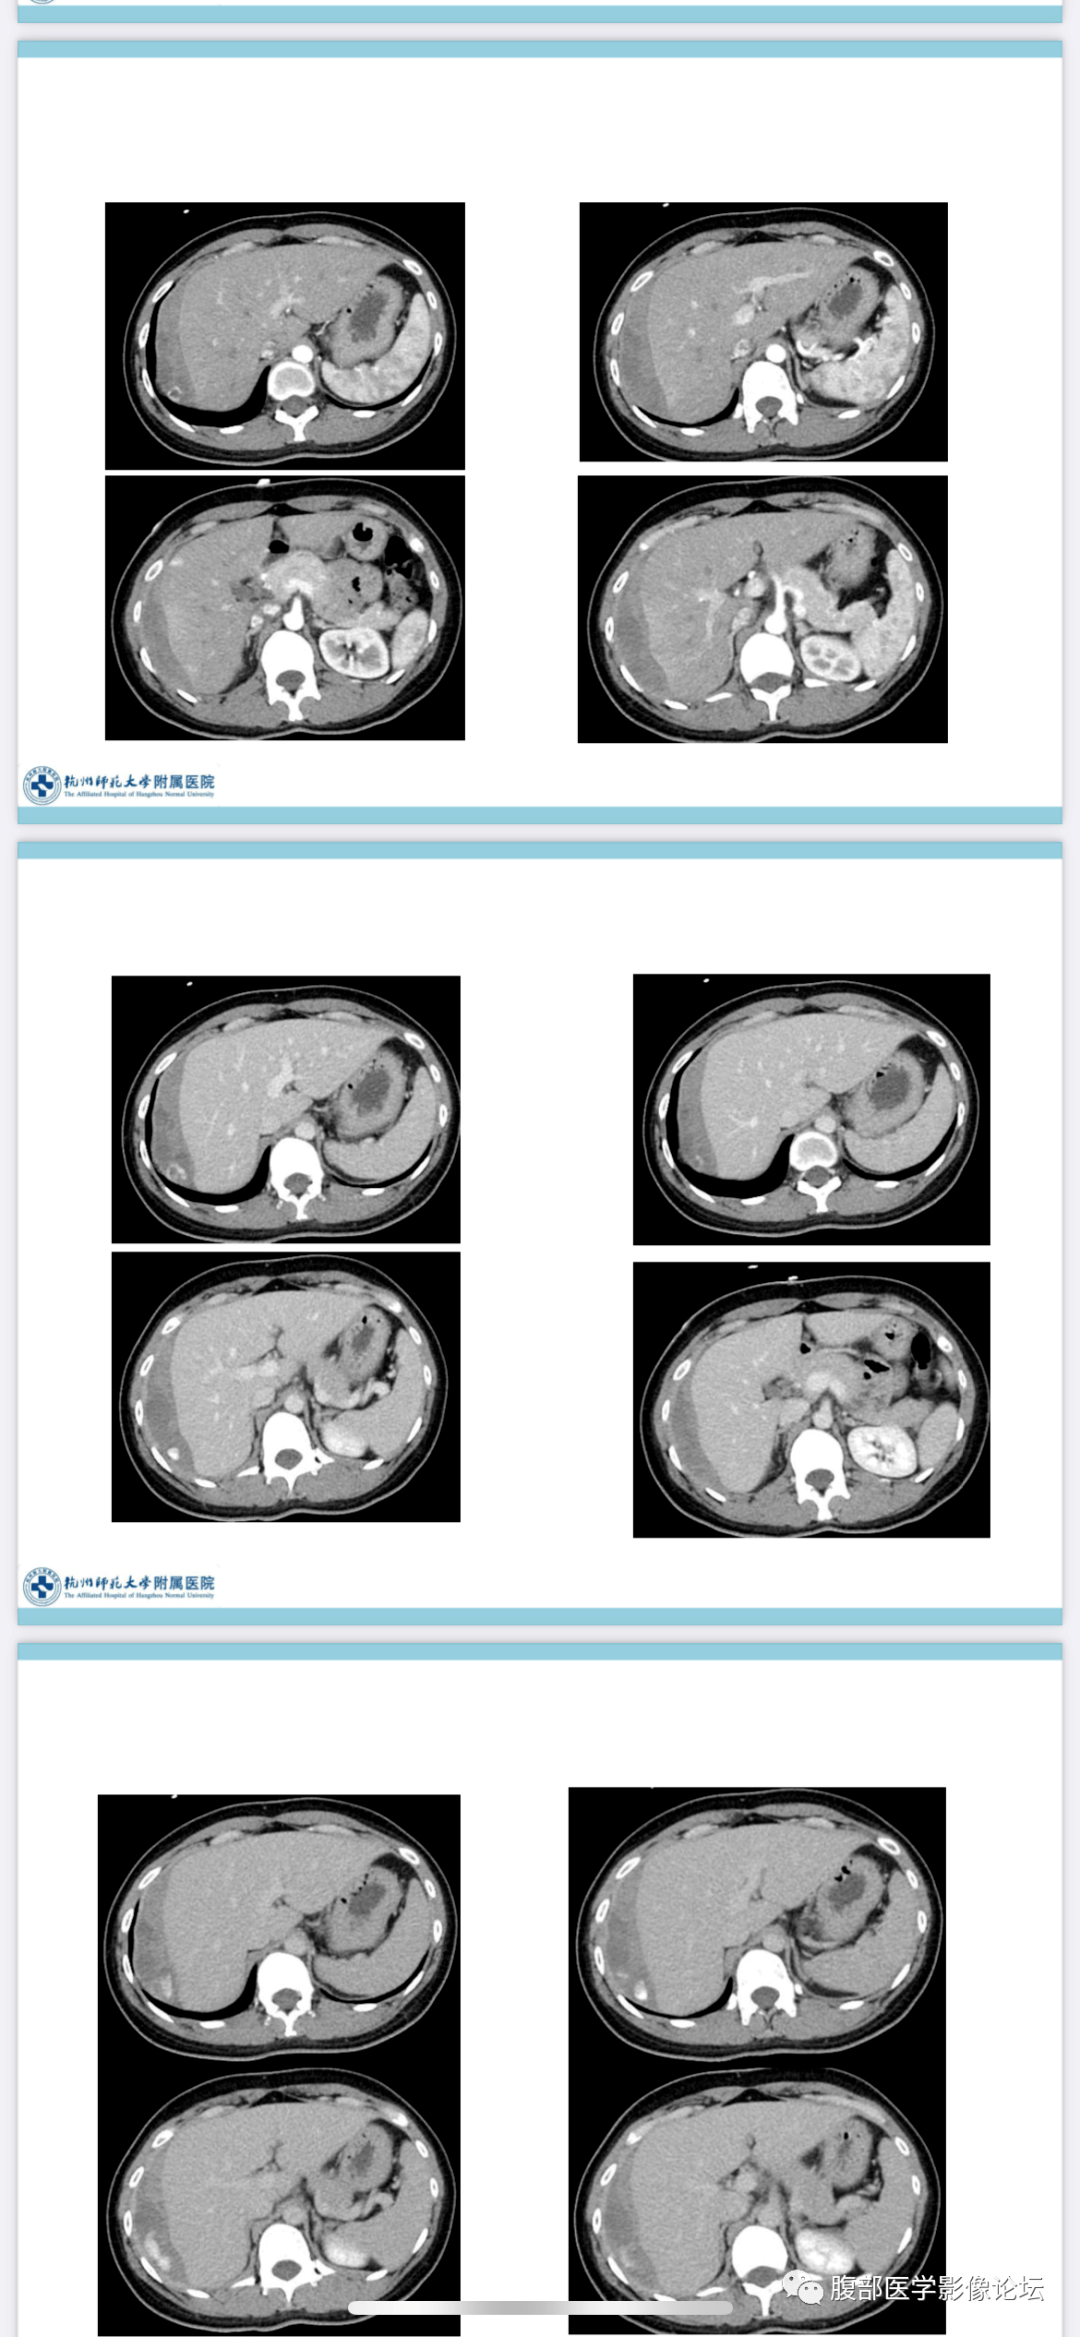

罕见病例丨肝周异位妊娠

图片尺寸1080x2337